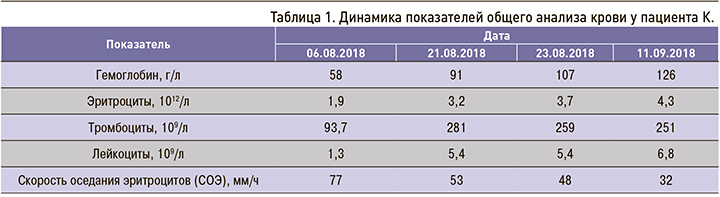

Динамика показателей общего анализа крови отражена в таблице 1.

Положительная динамика уровня гемоглобина крови была достигнута трансфузиями эритроцитарной массы. При дополнительном обследовании органов желудочно-кишечного тракта, сердца, почек патологии не выявлено. Развившаяся у пациента артропатия Жакку – ульнарная девиация пястно-фаланговых суставов и атрофия межостных мышц (рис. 1) – стала следствием поражения сухожильно-связочного аппарата и мышц, а не деструкции суставных поверхностей и хряща, что подтверждают рентгеновские снимки кистей рук (рис. 2).